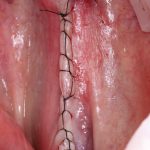

Осталось только наложить швы:

и подождать 3-4 месяца до интеграции имплантов.

Посмотрим на результат:

особенно на то, что внутри:

Обратите внимание, что между пересаженным костным блоком и принимающим ложем нет чёткой границы, а сам регенерат по цвету и структура, практически, не отличается от альвеолярного гребня. Это как раз то, что я называю хорошим результатом остеопластической операции. Нам останется только сформировать десну и установить коронки на интегрированные имплантаты.